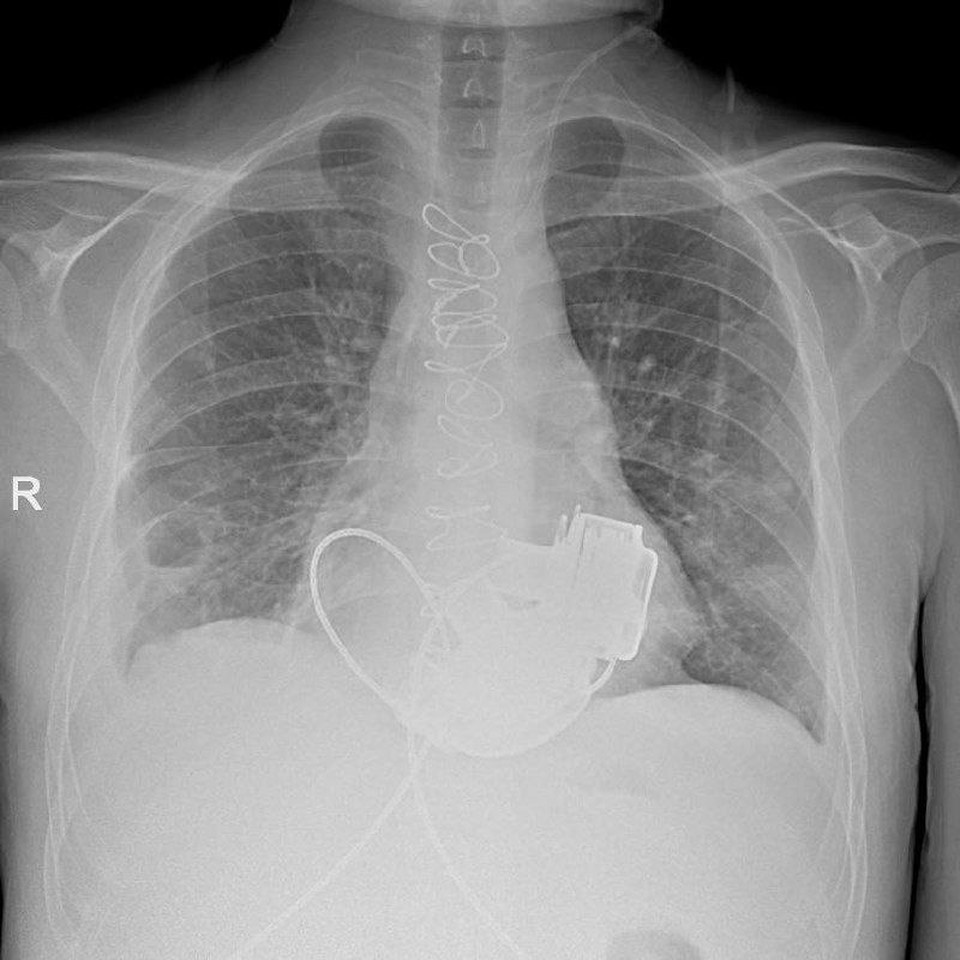

Петербуржец стал первым пациентом без естественного пульса. Фото: t.me/komzdravspb

Врачи провели сложную многочасовую операцию. Фото: t.me/komzdravspb

Сейчас Сергей готовится к выписке. Фото: t.me/komzdravspb